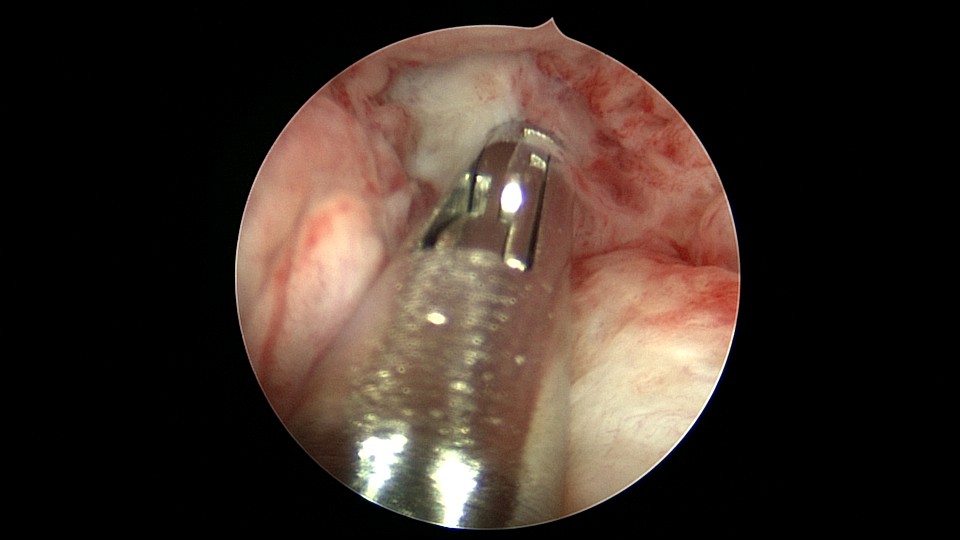

患者68岁,G3P1,顺产1次,安环42年,绝经20年,外院取环失败。子宫后位,宫颈及子宫萎缩,距宫颈内口1cm以上宫颈管封闭致密粘连,B超监护下异物钳分离粘连,打开进入宫腔的通道,艰难扩宫至6号扩宫棒,见O型环与两侧宫壁崁顿,异物钳无法取出,取环钩将环拉至宫颈外口,中弯钳牵拉,完整取出节育环,环变形,很艰难的取环经历。